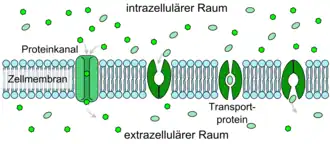

Die Blut-Hirn-Schranke muss trotz ihrer Funktion als Schutzbarriere auch den Transport von Nährstoffen zum Gehirn, beziehungsweise den Abtransport von Stoffwechselprodukten aus dem Gehirn, gewährleisten. Wasserlösliche Nährstoffe und Peptide überwinden die Blut-Hirn-Schranke im Wesentlichen durch spezifische Transporter oder spezielle Kanäle in der Zellmembran. Die meisten anderen löslichen Verbindungen passieren – wenn überhaupt – diese Barriere durch Diffusion.[11][15]

Erleichterte Diffusion

Eine spezielle Form der Diffusion durch die Zellmembran der Endothelien ist die erleichterte Diffusion (engl. facilitated diffusion). Lebenswichtige Nährstoffe wie Glucose und viele Aminosäuren sind zu polar und zu groß, um auf den bisher geschilderten Transportwegen in ausreichender Menge dem Gehirn über die Blut-Hirn-Schranke zur Verfügung gestellt zu werden. Für diese Moleküle gibt es in der Zellmembran ein spezielles Transportsystem: den sogenannten Carrier-vermittelten Transport. Beispielsweise wird die D-Glucose über den GLUT-1-Transporter in das Gehirn transportiert. Die Dichte der GLUT-1-Transporter ist auf der abluminalen Seite der Endothelien viermal höher als auf der luminalen, das heißt der zum Blut hin gerichteten, Seite.[120] Der Transport wird nur durch ein Konzentrationsgefälle ermöglicht und benötigt selbst keine Energie.

Neben der in relativ großen Mengen vom Gehirn benötigten D-Glucose gibt es außer GLUT-1 eine Reihe von weiteren speziellen Transportern. Sehr viele dieser Transporter sind aus der Familie der Solute Carrier (SLC), darunter beispielsweise MCT-1 und MCT-2, die eine Reihe von kurzkettigen Monocarbonsäuren – unter anderem Lactat, Pyruvat, Mevalonat, verschiedene Butyrate und Acetat – transportieren. SLC7 transportiert kationische Aminosäuren (Arginin, Lysin und Ornithin). Vom Modellorganismus Maus sind bisher 307 SLC-Gene bekannt. Davon werden über 200 im Choroid plexus und in anderen Gehirnbereichen exprimiert. An der Blut-Hirn-Schranke der gleichen Art wurden bisher allerdings nur 36 nachgewiesen. Etwa 70 % von den 36 haben Genprodukte, die am Transport von Nährstoffen, Vitaminen, Hormonen und Spurenelementen beteiligt sind. Besonders stark sind an der Blut-Hirn-Schranke die Thyroid-Transporter SLC16a2 und SLCO1c1, der Sulfat-Transporter SLC13a4, der L-Ascorbinsäure-Transporter SLC23a2, der Aminosäure-Transporter SLC 38a3 und der Folat-Transporter SLC19a1 exprimiert.[121] Ascorbinsäure (Vitamin C) wird in oxidierter Form über die Glukosetransporter dem Gehirn zugeführt.[122]

Die Transporter können als Uniporter (nur in eine Richtung), als Symporter in zwei Richtungen und als Antiporter in entgegengesetzter Richtung arbeiten.[123]

Aktiver Transport

Bei den zuvor beschriebenen passiven Arten des Transportes durch das Endothel gelangen die Moleküle ohne zusätzlichen Bedarf an Energie zum Gehirn, beziehungsweise vom Gehirn weg. Sie folgen dabei dem jeweiligen Konzentrationsgefälle. Mit aktiven Transportern, sogenannten „Pumpen“, ist ein Transport auch gegen einen Konzentrationsgradienten möglich. Dabei wird allerdings direkt oder indirekt Energie in Form von Adenosintriphosphat benötigt.[99] Findet der aktive Transport vom Blut zum Gehirn statt, so spricht man von Influx („Einströmen“). In umgekehrter Richtung spricht man von Efflux („Abfluss“).